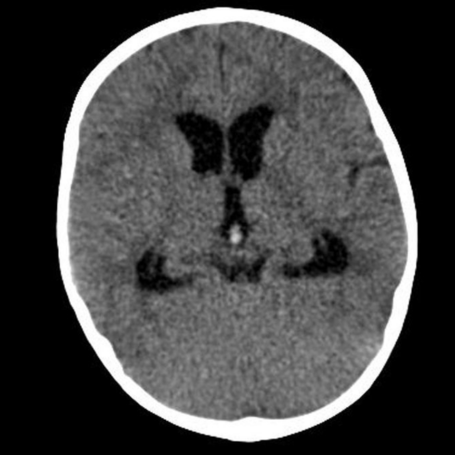

Hidrocefalia no comunicante

Tipos: La hidrocefalia no comunicante (u obstructiva) ocurre cuando hay un bloqueo en el flujo del líquido cefalorraquídeo (LCR) dentro del sistema ventricular, impidiendo su circulación normal. Puede ser aguda o crónica y afectar uno o varios ventrículos.

Diagnóstico: Se realiza mediante evaluación clínica y estudios de imagen como tomografía computarizada (TAC) y resonancia magnética (RM), que permiten identificar la dilatación ventricular y el sitio de obstrucción. También se evalúan signos de presión intracraneal elevada.